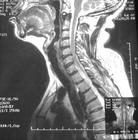

2.CT與MRI(磁共振成像)檢查

顯示脊柱裂合併脊髓栓系(圓錐位置低,與局部粘連,可合併囊腫或脂肪瘤)。